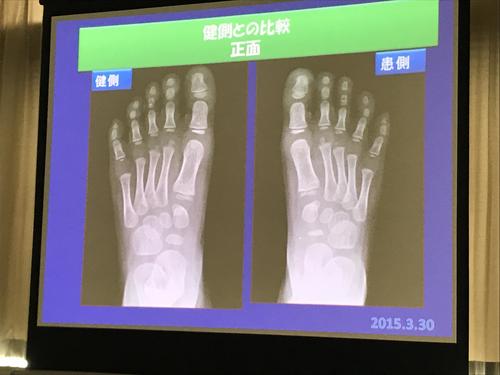

サッカー選手に多い、足の甲のケガ Impingement exostosis(インピンジメント エクソトーシス)、

バレエダンサーに多い三角骨障害&距骨後突起障害、

その他、足の疲労骨折、Jones骨折、小児のIselin病などのお勉強。